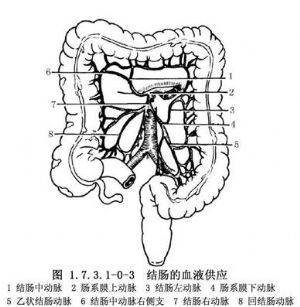

右半结肠的血液供应(图1.7.3.1-0-3)来自肠系膜上动脉分出的结肠中动脉的右侧支、结肠右动脉和回结肠动脉。约25%病人无结肠中动脉,而由结肠右动脉的一支代替,有的病人有两条结肠中动脉。横结肠的血液供应来自肠系膜上动脉的结肠中动脉。左半结肠血液来自肠系膜下动脉分出的结肠左动脉和乙状结肠动脉。静脉与动脉伴行,最终注入门静脉。有的结肠左动脉与结肠中动脉之间无吻合,也很少有边缘动脉,此处称Roilan点,手术时应加注意。淋巴管也与血管伴行,经过肠系膜上、下动脉根部淋巴管至腹主动脉旁淋巴结,最后注入胸导管。因此,在根治结肠癌时,须将该部结肠动脉所供应的整段肠管及其系膜全部切除。